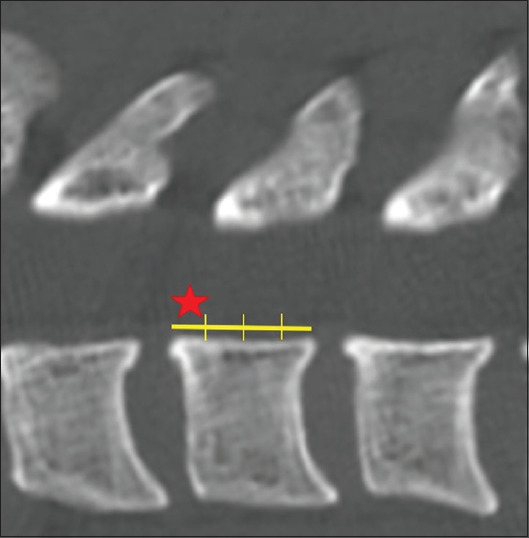

背景:侧块椎弓根内螺钉(LMIS)固定于2021年被引入,作为一种安全简单的替代方法固定下颈椎治疗各种颈椎疾病。本研究的目的是评估和比较这种新技术的螺钉拔出强度与其他两种主要方法,经椎弓根螺钉(TPS)和侧块螺钉(LMS)方法的轨迹。方法:203例在我院接受宫颈计算机断层扫描(CT)的患者纳入研究。使用从C3到C6的颈椎轴向切片选择三个轨迹中的每个感兴趣的区域,并计算CT数(Hounsfield单位)。结果:共收集4872个数据点。患者平均年龄59.5岁。男女比例为135:68。65岁以上患者93例。TPS的平均CT数为511.9,LMS为473.1,LMIS为598.5。即使对性别和年龄进行了调整,三种轨迹的CT数也有显著差异。结论:LMIS是一种有希望的替代常用方法用于下轴颈椎固定,具有显著的拔出强度。这种方法值得许多患者考虑。

Methods: Two hundred and three patients who underwent a cervical computed tomography (CT) scan at our institution were included in the study. A region of interest for each of the three trajectories was selected using axial slices of the cervical vertebra from C3 through C6, and the CT number (Hounsfield unit) was calculated.